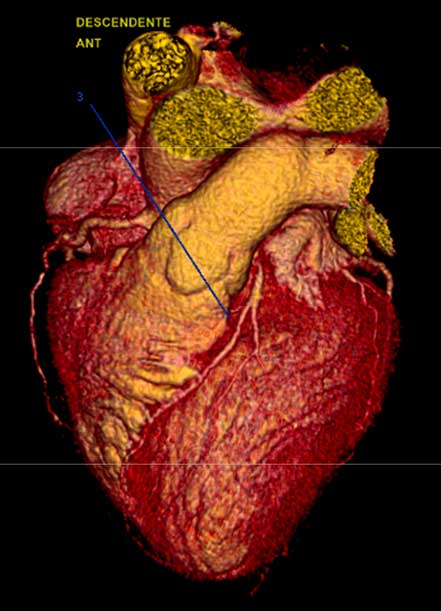

- Angiotomografía coronaria

- Imagen cardiovascular

- Enfermedades de las arterias coronarias o coronariopatía